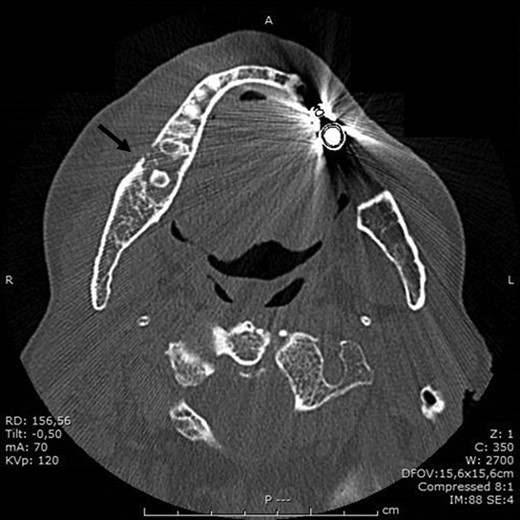

BRONJ was clinically diagnosed at the patient’s first visit based on her history and was confirmed radiologically by the dental x-ray and CT performed in July 2016. X-rays showed reduced density of the alveolar bone edges, particularly on the right where the alveolar bone crest profile was rather irregular. A small residual root was present in the molar region on the right. The inferior alveolar nerve canal was clearly recognizable, on both sides.

In November 2016, the patient underwent surgery under general anaesthesia. After infiltration of a local anaesthetic (mepivacaine + adrenaline 1:200 000), surgery was carried out as described: mucoperiosteal incision of the right mandible with mesial and distal drainage, extensive fistulectomy of the hyperplastic mucose membrane, which showed multiple fistulas, skeletonisation and exposure of abundant necrotic tissue; debridement of hyperplastic-inflammatory tissue and ostectomy of necrotic bone with osteoplasty of sharp edges; positioning of HAM and water and hermetic suture with Polisorb 3/0 absorbable braided thread (Fig. 2A–E). Histological examination confirmed the presence of inflammation and the diagnosis of osteonecrosis. The mesial and distal bone curettage margins were dictated by the x-ray images (Fig. 3) identifying above all the radio-opaque areas, often associated with a periosteal reaction, as well as by the need to remove any bone sequestra present. The imaging was also associated with the intraoperative assessment of the macroscopic appearance of the bone and in particular the signs of bleeding from the cortex and medulla. The HAM was 3 × 3 cm2 in size and was positioned over the curetted area and under the mucosal flap.

BRONJ had been clinically diagnosed at the patient’s first visit and confirmed radiologically by the dental x-ray and CT performed in September 2016, which showed marked demineralization of the anterior portion of the orbital ethmoid wall on the right, left mandibular osteonecrosis in the premolar region, a small periapical granuloma in position 44 and diffuse upper and lower alveolar atrophy.

In November 2016 the patient underwent surgery under general anaesthesia (same technique used for the first patient described) (Fig. 4A–D). The mesial and distal bone curettage margins were dictated by the x-ray images (Fig. 5) which identified above all the radio-opaque areas, often associated with a periosteal reaction, as well as by the need to remove any bone sequestra present. The HAM was 3 × 3 cm2 in size and was positioned over the curetted area and under the mucosal flap.